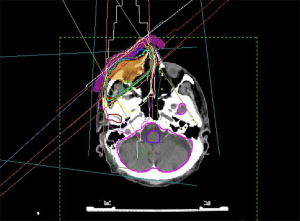

在放射治疗的背景下,所有这些照射技术都被合适地使用。目标是在所有皮肤层中实现良好的剂量分布。因此,照射计划将肿瘤区域围在肿瘤学上足够的安全范围内,通常为 0.5 ~1.5 cm。总剂量选择在 20 ~77 Gy 之间,具体取决于肿瘤情况[46,47]。图3 显示了眼周BCC的治疗计划。

良好的眶周放射治疗计划要求在整个BCC达到肿瘤放射有效剂量,同时保护对辐射敏感的眼睛结构,例如角膜、晶状体、视网膜、视神经和泪腺,包括带有睫毛的眼睑[41,47,48]。然而,辐射引起的副作用可能以不同的形式发生。最常见的是睫毛脱落、干燥症状、角膜表面障碍直至结膜化以及辐射诱发的白内障。放射性视网膜病变和放射性视神经病变在BCC的治疗中很少见,通常应通过良好的放射计划来避免[49,50]。眼科医师和放射治疗师之间的合作有助于以最小化副作用的方式设计放射的范围。特别是在经皮照射中,眼睛的运动控制是必不可少的,这通常是通过患者在照射过程中注视着相机实现的。